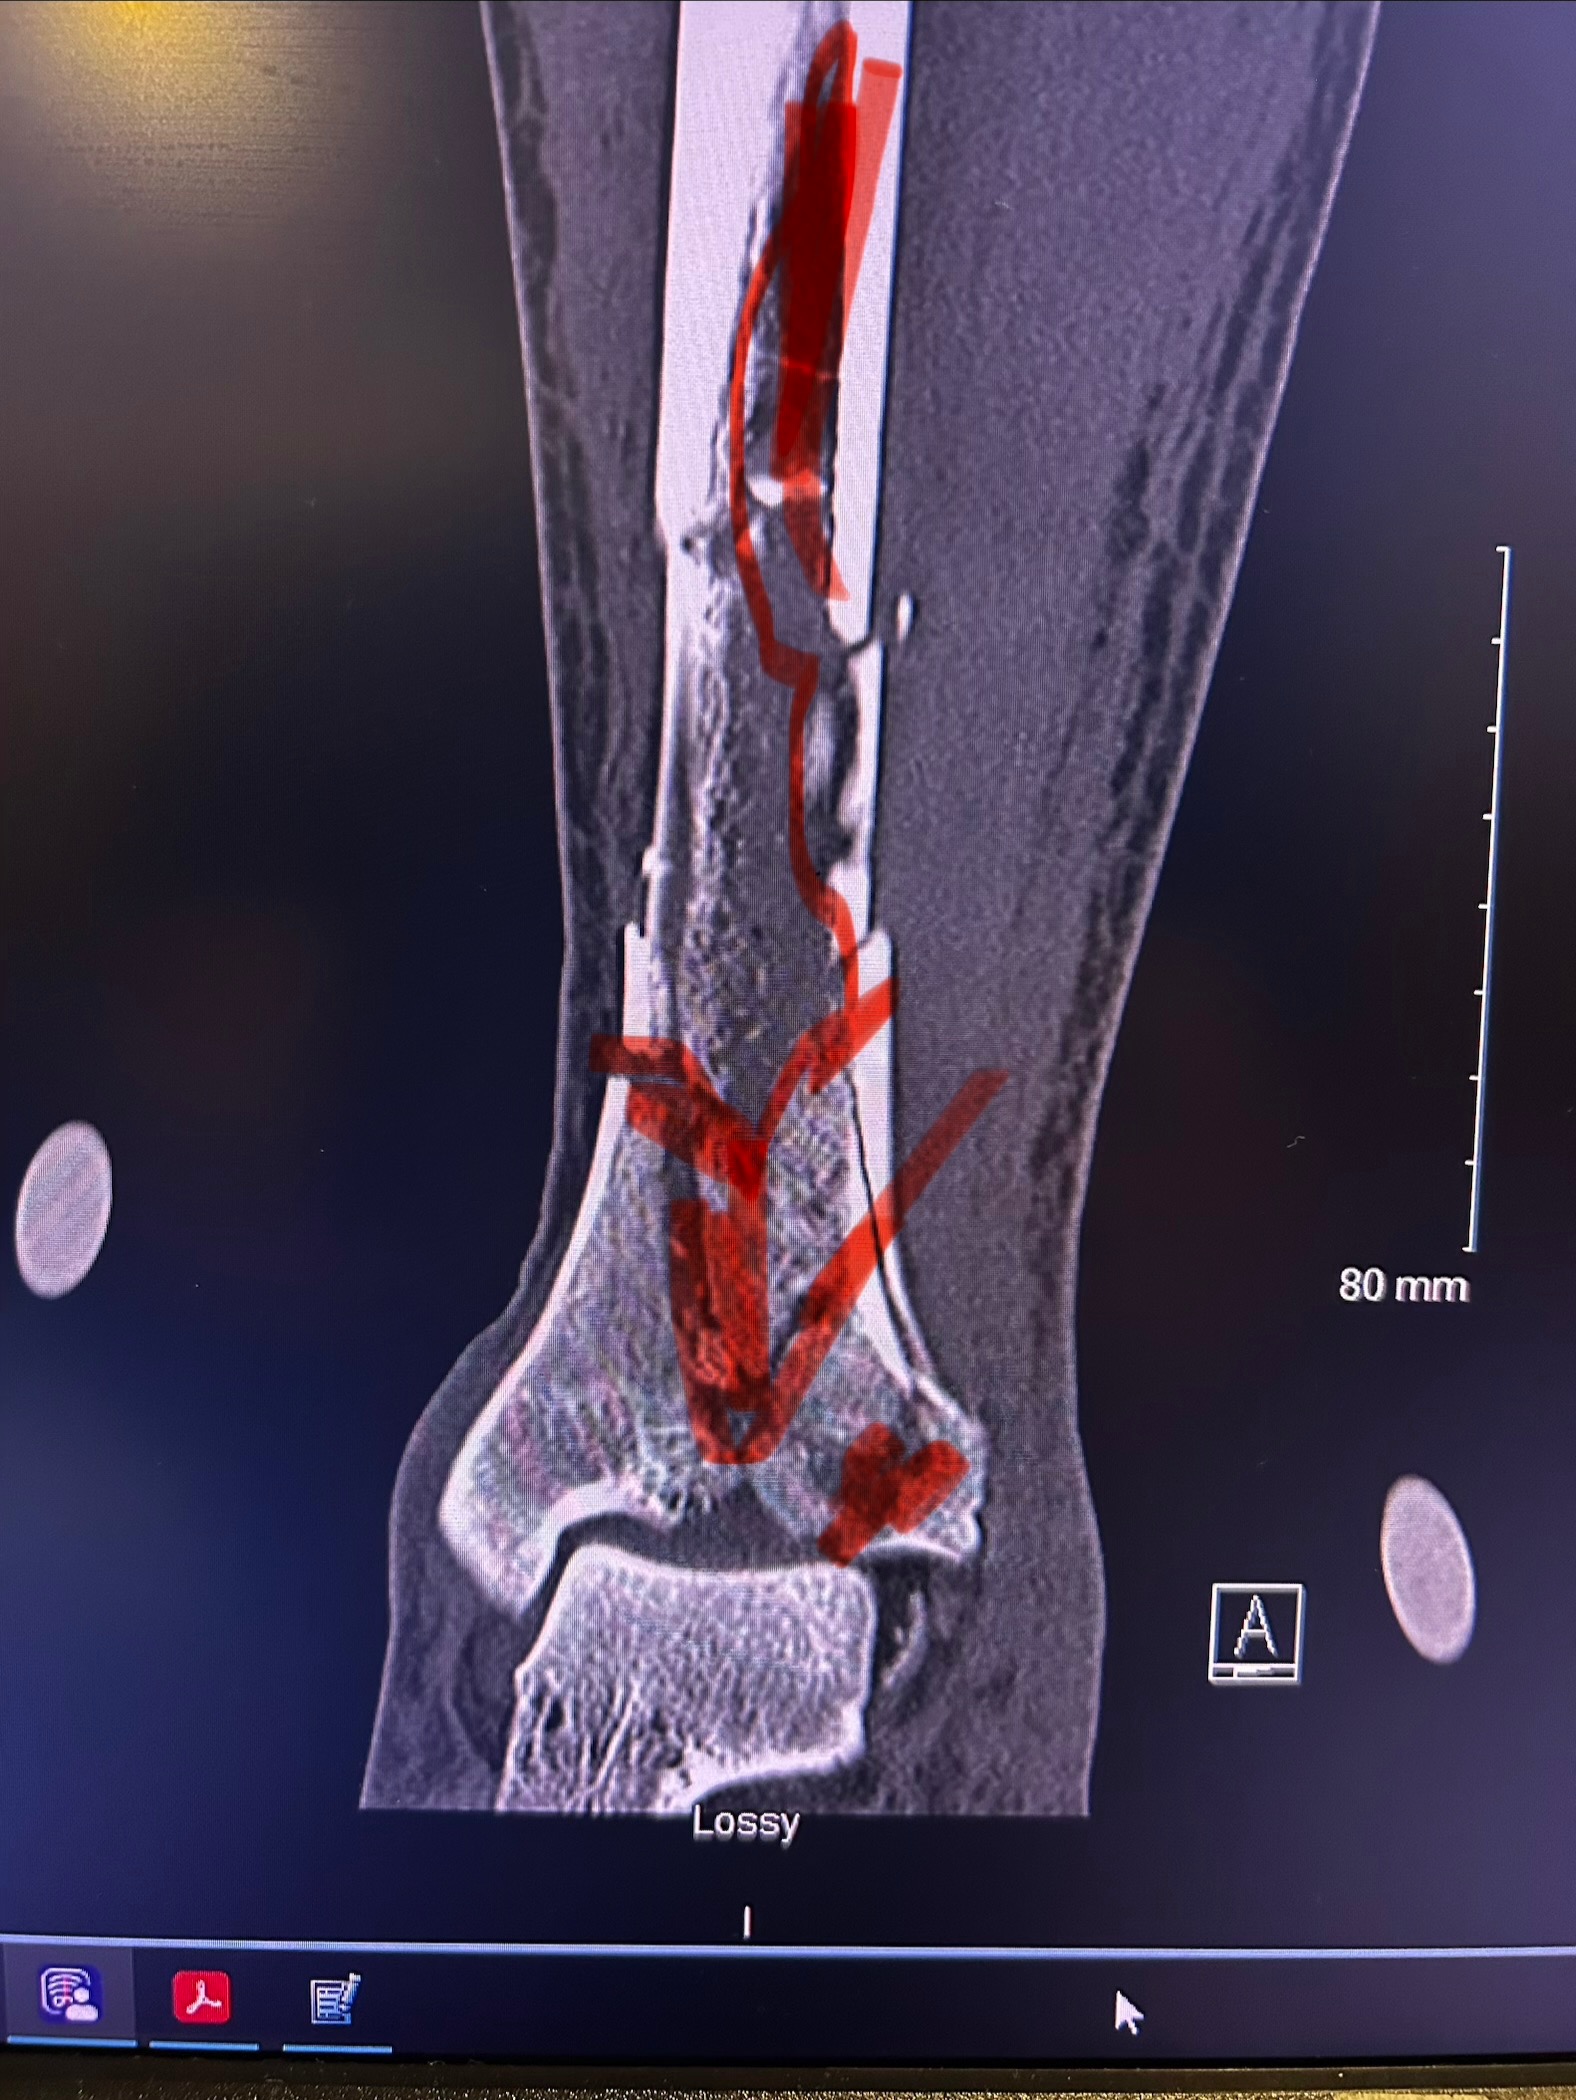

On January 22nd at 10:49 AM, I got the call no one ever wants to receive. It was John, screaming that he had fallen. In that moment, everything stopped. John fell approximately 20–25 feet, causing severe injuries from his left knee down. We are incredibly grateful and beyond blessed that he is alive today, because this situation could have ended very differently.